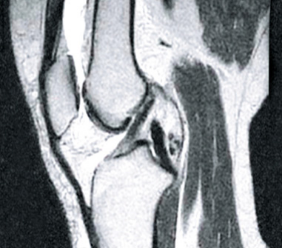

PRZED

PO

Na zdjęciu po lewej widać puste przestrzenie w obrębie torebki stawowej powstałe na skutek zbytniego uwodnienia tkanki. Po kuracji struktura mazi stawowej się odbudowała (zdjęcie po prawej), odzyskała lepko-sprężystą konsystencję i właściwości poślizgowe. Kości są odpowiednio „naoliwione”, dzięki czemu nie trą o siebie, ponieważ funkcje amortyzujące stawu zostały przywrócone.